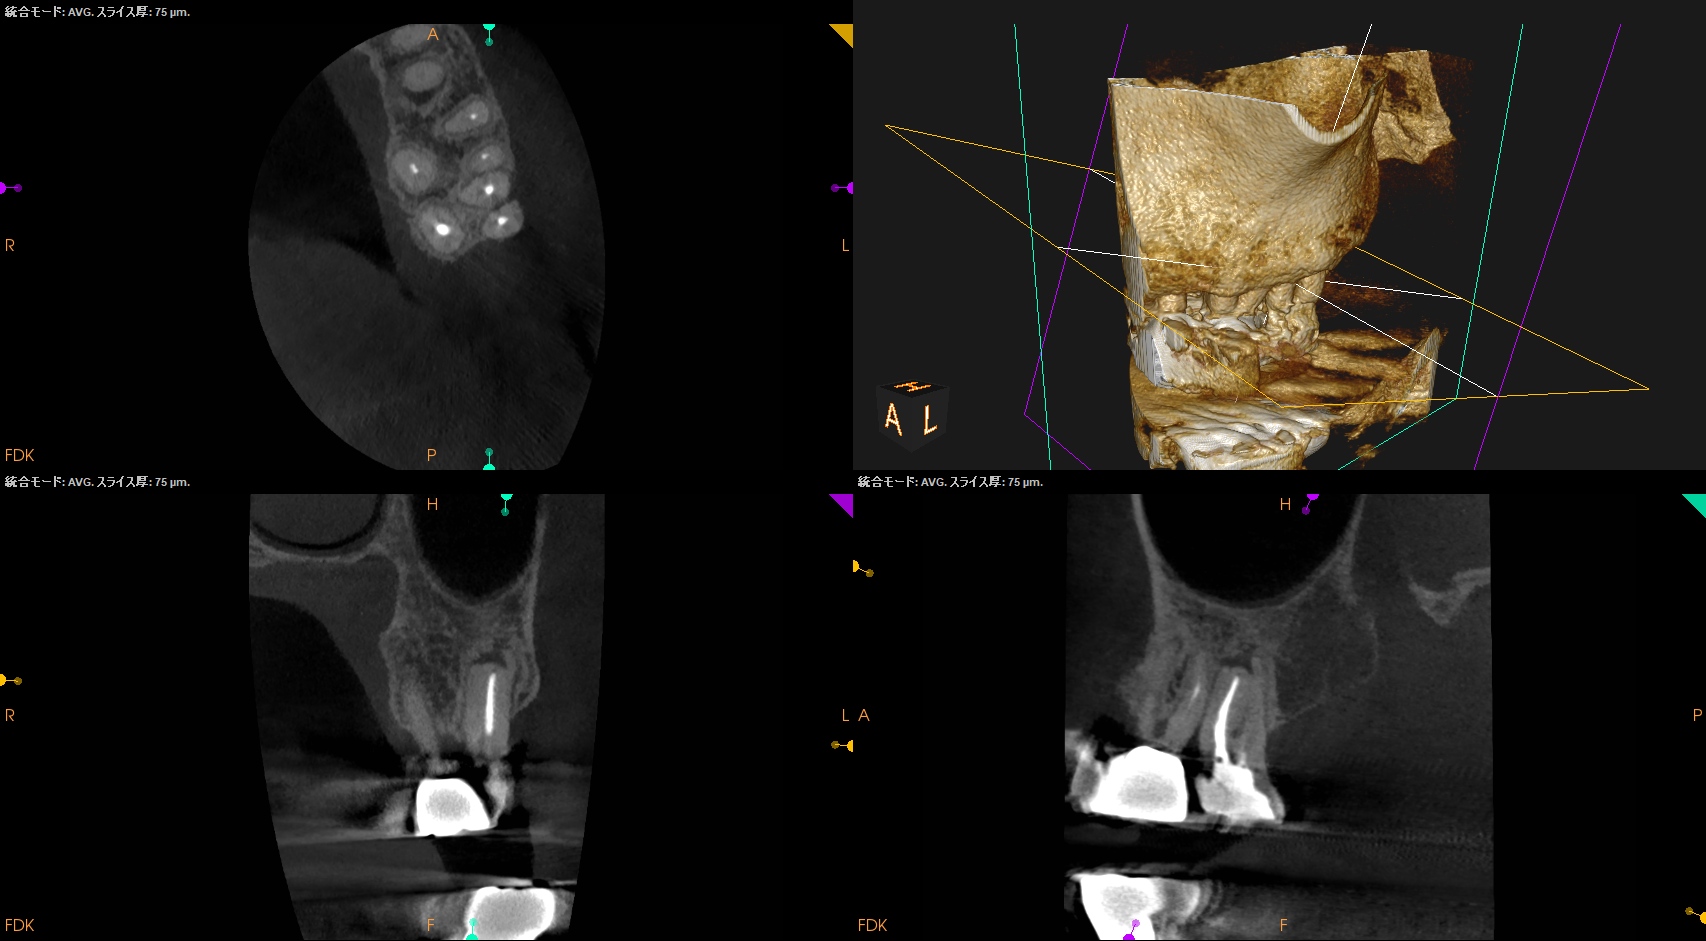

CBCT(2025.5.8)

MB

MBは全く根管形成していないし、根尖病変もある。再根管形成必須だ。

MB2はMB1の近傍にある。

DB

DBは病変がない。

石灰化も進行している。

P

P根にも根尖病変がある。

ここも再根管形成が必要だ。